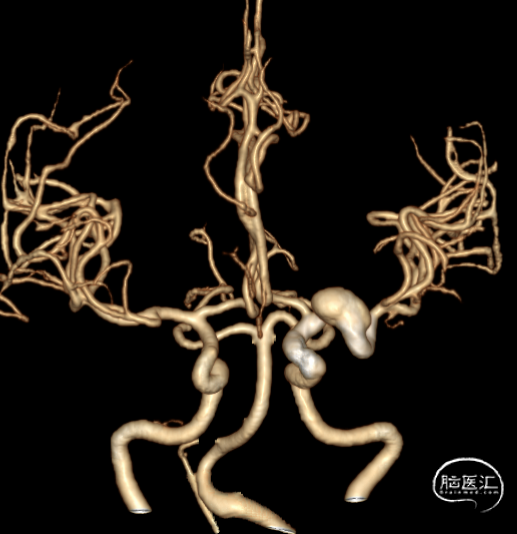

2024年4月1日 DSA

L ICA

L ICA 3D

AN长径9.14mm

远端血管大脑中直径2.34mm、近端颈内末端4.25mm